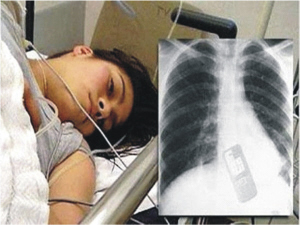

为阻男友查短信吞下手机

据媒体报道,这位巴西女孩名叫安德丽亚,今年十九岁。当男友向她提出要检查她的手机短信后,安德丽亚曾试图拒绝,但是最终还是在男友惊讶的目光下,孤注一掷地吞掉了自己的电话,以绝后患。在吞下了电话后,安德丽亚立刻被送往了附近的医院抢救。